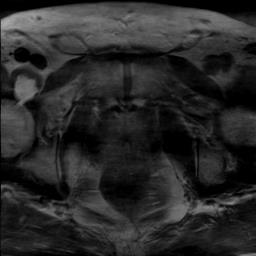

Modern deep neural networks struggle to transfer knowledge and generalize across diverse domains when deployed to real-world applications. Currently, domain generalization (DG) is introduced to learn a universal representation from multiple domains to improve the network generalization ability on unseen domains. However, previous DG methods only focus on the data-level consistency scheme without considering the synergistic regularization among different consistency schemes. In this paper, we present a novel Hierarchical Consistency framework for Domain Generalization (HCDG) by integrating Extrinsic Consistency and Intrinsic Consistency synergistically. Particularly, for the Extrinsic Consistency, we leverage the knowledge across multiple source domains to enforce data-level consistency. To better enhance such consistency, we design a novel Amplitude Gaussian-mixing strategy into Fourier-based data augmentation called DomainUp. For the Intrinsic Consistency, we perform task-level consistency for the same instance under the dual-task scenario. We evaluate the proposed HCDG framework on two medical image segmentation tasks, i.e., optic cup/disc segmentation on fundus images and prostate MRI segmentation. Extensive experimental results manifest the effectiveness and versatility of our HCDG framework.